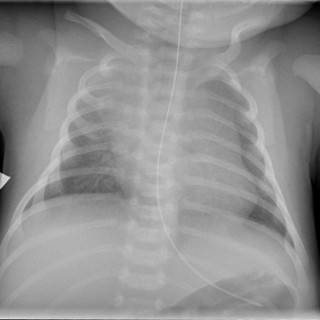

Medisinen i bilder